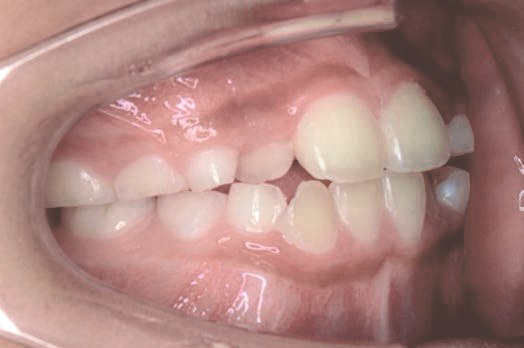

下の奥歯が内側に傾いて、舌の位置が悪く、鼻がつまって口呼吸の状態でした。扁桃腺がよく腫れ、風邪をひきやすく、いびきもあるようでした。

治療を終えて

装置で上あごを拡大し、下の歯の位置を整え、前歯の並びを整えました。お口のトレーニングの効果で鼻詰まりと、いびきも改善。たった1年でこの変化が見られました。もちろん歯は1本も抜いていません。

主訴・治療内容 他院にて「抜歯した上で、ワイヤーを付け、5年かけて治療する」と言われ、他の方法はないのかとネットで調べたところ、当院を知り無料相談に来院されました。